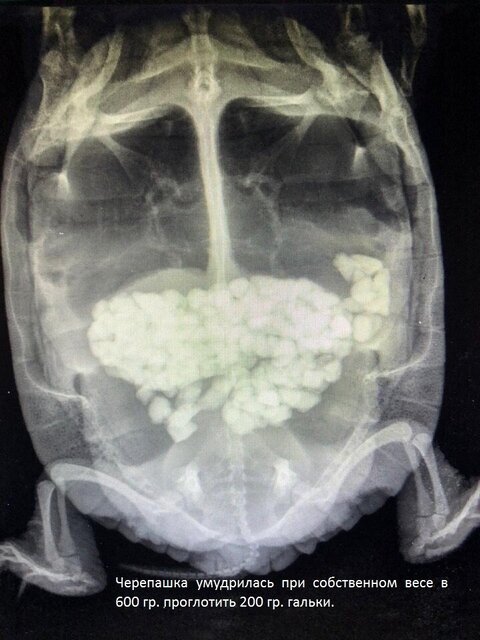

Не ведаю, как обстоят дела у кур и динозавров, но у черепах это может выглядеть примерно так:

В природе они не живут, а выживают, причем выживают самые генетически одаренные особи: быстрые, активные, агрессивные, прожорливые, неприхотливые, хитрожопые и сообразительные, а большая часть погибает еще в детстве - естественный отбор называется. Едят они в природе камни или нет, опять же не могу сказать наверняка, но если и съедают, то так же отлетают с закупоркой кишечника на радугу, после чего их оперативно съедают другие, поэтому диагностики и статистики по таким темам нет. Конкретно в условиях террариума наблюдается такое явление, как изменение пищевого (и не только) поведения, когда черепаха, будучи долгое время равнодушной к декору и оборудованию, в любой момент может начать кусать и глотать камни, ракушки, искусственное покрытие мостика, мелкий пластиковый декор, присоски и провода от фильтра и нагревателя и тд - результат на фото выше.